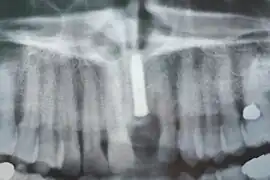

Implants en place. Notez qu'il y a moins d'implants que de dents sur la prothèse.

Prothèse totales fixes sur implants

Elles ont en règle réalisables sur six implants (selon des modalités bien précises pour l'observation desquelles le poseur d'implant doit avoir les qualifications requises). Selon la récession osseuse du patient à la suite de la perte de ses dents, on réalisera une prothèse sans ou avec fausse gencive. Moins coûteuses que les bridges, ces prothèses sont moins longues à réaliser. Rien n'empêche cependant le patient de faire remplacer sa prothèse résine par une prothèse céramique après une période d'observation de deux ans.

Radiographie des six implants

Contrôle de la cicatrisation à une semaine de l'intervention